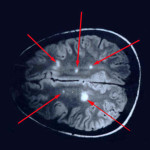

I polifenoli dell’uva nel vino rosso proteggono dal cancro al seno.Essi hanno dimostrato anche di ridorre le cellule tumorali nel fegato e ossa, in vari studi. Mentre le uve bianche hanno relativamente basso in contenuto di polifenoli, più di 200 polifenoli sono stati identificati nel vino rosso, tra cui il resveratrolo, quercetina e catechina. polifenoli sono stati trovati anche utili per rafforzare le reti neurali, impedendo in tal modo le malattie neurodegenerative come l’Alzheimer. Gli studi hanno dimostrato che questi fitochimici combattono lo strss ossidativo nelle cellule del cervello e possono invertire deficit cognitivo-comportamentali.